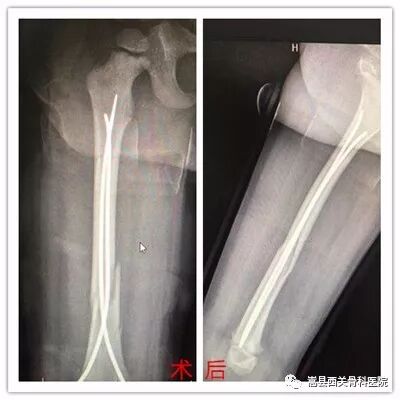

弹性髓内针技术具有创伤小、手术操作简单、创伤小,骨折复位满意、固定简便可靠,骨折愈合快,住院时间短等特点。该技术已得到世界范围内小儿骨科医生的广泛推崇,成为治疗儿童长骨骨折的首选方法。

我院创伤骨一科根据小儿骨折的特点,成功引入了国际上治疗儿童骨折的新技术——儿童弹性髓内针技术,并取得了满意的疗效。

典型病例: